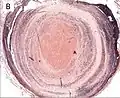

Thrombus showing circumferential lines of Zahn. -